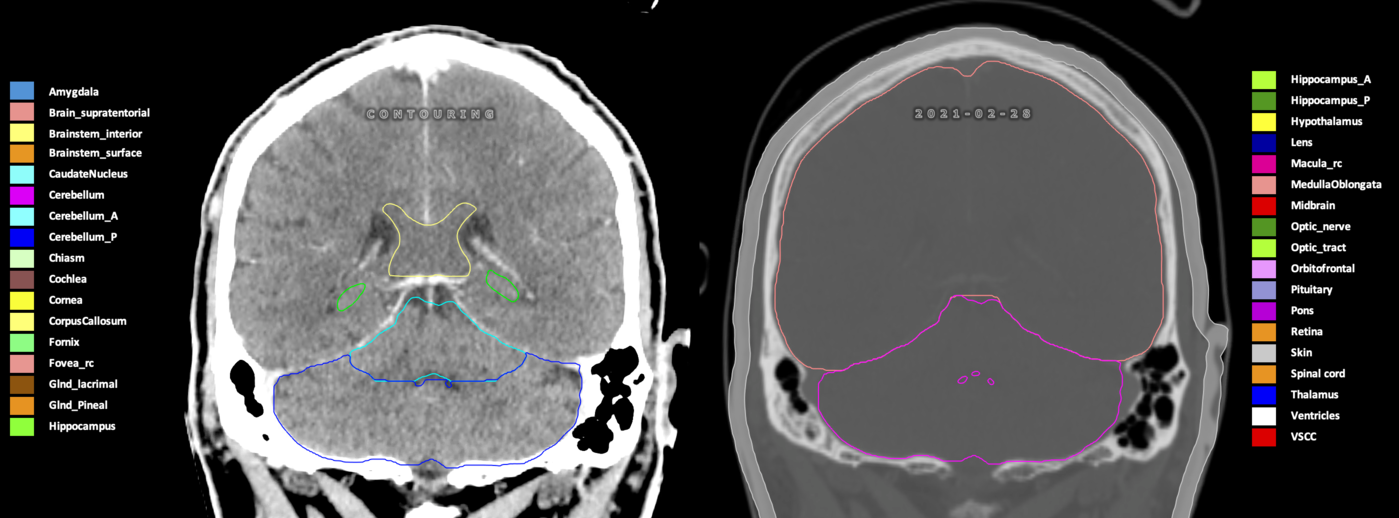

Eekers et al. have published an international neurological atlas for contouring of organs at risk in consensus with the European Particle Therapy Network (EPTN) in 2018 and an update in 2021. The purpose of this consensus atlas is to decrease inter- and intra-observer variability in delineating OARs relevant for neuro-oncology.

Included are all OARs known to be relevant for radiation-induced toxicity in neuro-oncology: brain, brainstem (midbrain, pons, medulla oblongata), chiasm, cerebellum (anterior & posterior), cochlea, cornea, hippocampus (anterior & posterior), hypothalamus, lens, lacrimal gland, optic nerve, pituitary, skin, and vestibular & semicircular canals. To further facilitate research on cognition, vision and radiological changes after irradiation of the brain, potential clinically-relevant OARs are included: amygdala, caudate nucleus, cerebellum (anterior & posterior), corpus callosum, fornix, macula, optic tract, orbitofrontal cortex, periventricular space (PVS), pineal gland, and thalamus.

Three-dimensional delineation of the 25 consensus OARs for neuro-oncology are shown on CT (WW/WL 120/40, 3000/600), 3T MR images, (T1Gd, T2FLAIR 1mm) and 7T MR (MP2RAGE 0.7 mm). All are presented in transversal, sagittal and coronal view.